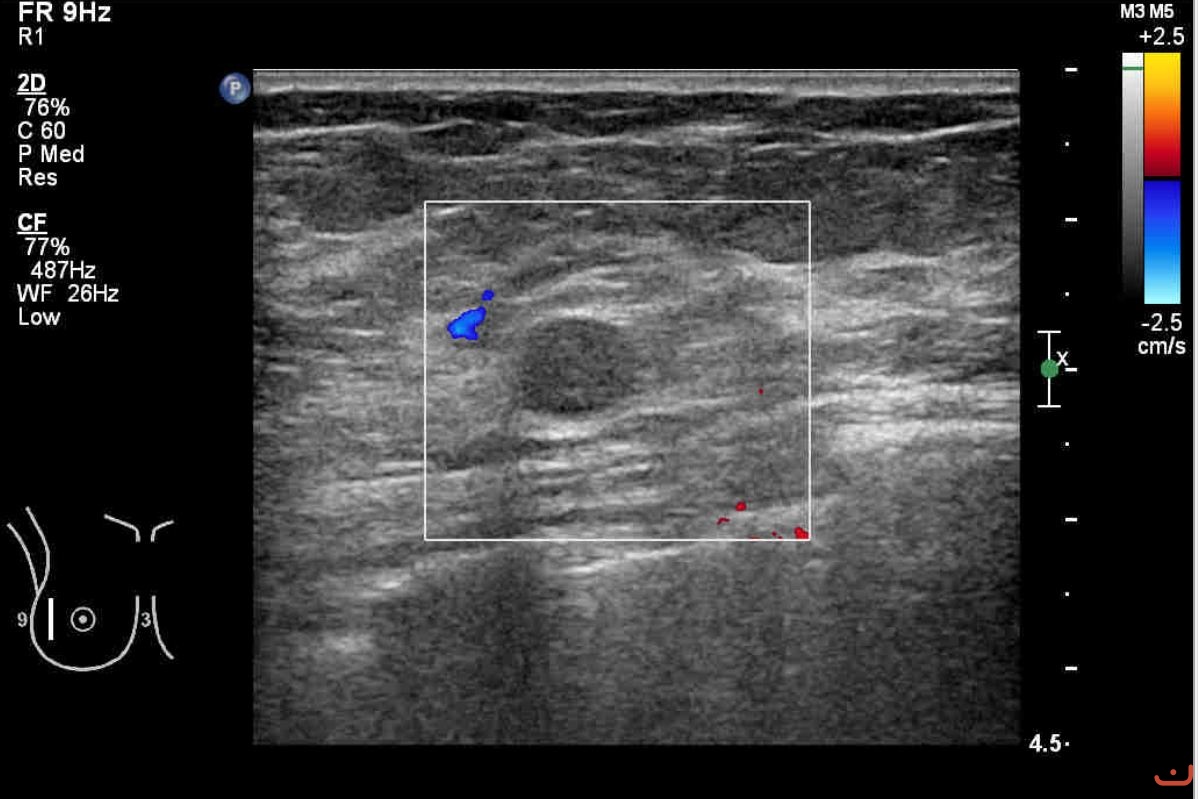

Benign solid mass

Sunday, 16 August 2015

114.12 KB (1198 x 799 px)